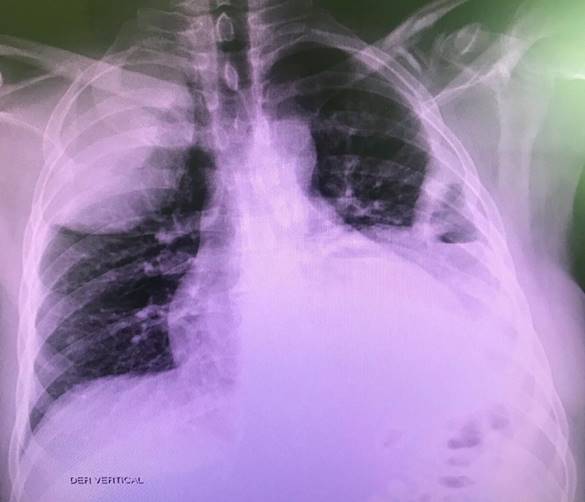

Al examen físico se encontró disminución de la ventilación en pulmón izquierdo, además de masa de 10 cm por 15 cm, dolorosa y eritematosa, localizada en segundo espacio intercostal izquierdo con línea axilar anterior (Figura 1). Por lo anterior, se solicitaron paraclínicos reportados así: Creatinina y BUN normales, hemoleucograma con hemoglobina (hb) de 10.8, hematocrito 31.7, leucocitos 16 700, plaquetas 627 000, proteína C reactiva (PCR) 31.75. También se pidió radiografía de tórax que evidencia colecciones pleurales bilaterales, nivel hidroaéreo del lado izquierdo y las fracturas descritas anteriormente (Figura 2).

Ante los hallazgos en la radiografía simple, se decidió complementar el estudio con una TAC de tórax con contraste, que reportó colecciones pleurales bilaterales con extensión a la pared del tórax (con compromiso de la musculatura intercostal y escalénica en el lado derecho; en el lado izquierdo estaba comprometido el pectoral) en relación con Empiema Necessitatis (Figura 3, Figura 4).